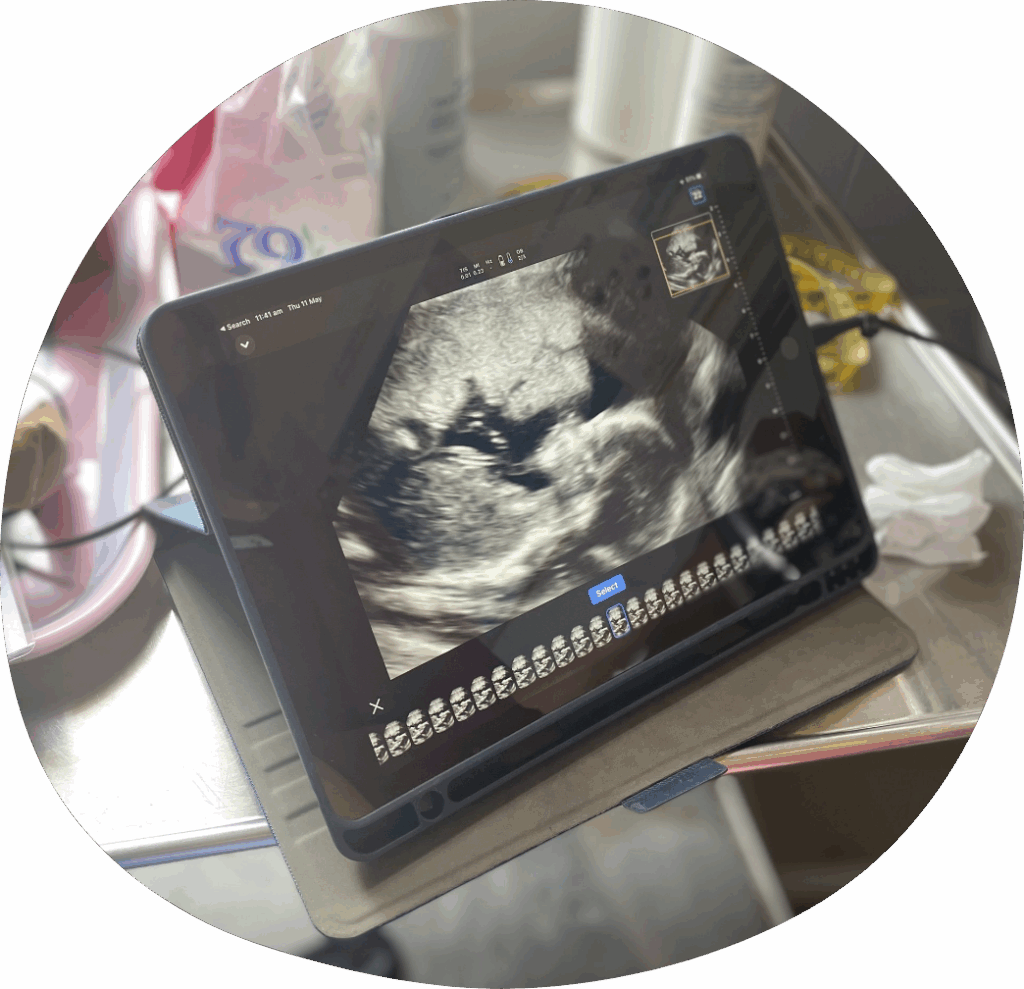

Ultrasound – seeing is believing

Innovative pilot ultrasound program in Cambodia

In Cambodia, financial, geographic and cultural barriers limit healthcare access for pregnant women. So in 2022, six Cambodian health centres were selected to be a part of an innovative initiative, the first of its kind in Cambodia.

This pilot program involved the introduction of handheld, point-of-care ultrasounds in rural health centres and was designed to improve maternal care for a combined population of 69,742 people. The program proved to be a transformative health strategy positively impacting the lives of mothers and babies in an underserved part of the world.

Throughout the pilot, the Cambodian midwives from the six health centres underwent a profound evolution, transitioning from unfamiliarity to competency in the utilisation of handheld point-of-care ultrasound for antenatal care provision, specifically in the early detection of obstetric complexities.

Prior to the commencement of the project, these midwives had no prior knowledge, understanding or experience in utilising ultrasound technology for antenatal care. Through comprehensive training and hands-on mentorship, they not only acquired a new life-saving skill but have seamlessly integrated it into their daily practice.